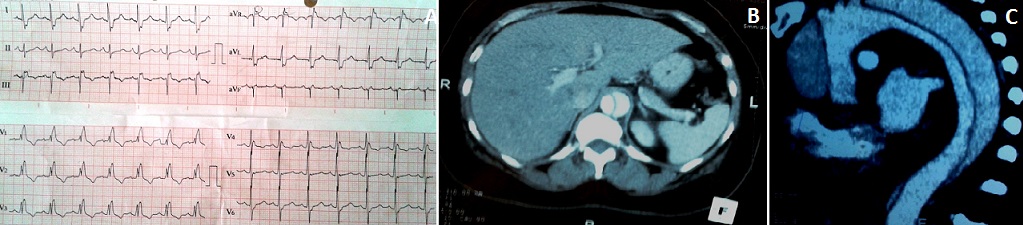

Il s'agit d'une femme de 52 ans, hypertendue, tabagique et obèse (IMC à 32,46 kg/m2), sans facteurs de risques thromboembolique évident, hospitalisée pour une douleur thoracique gauche à irradiation dorso-lombaire associée à une dyspnée. L'examen clinique à l'entré objectivait une pression artérielle gauche à 100/60 mmHg, une tachycardie à 100/min, une désaturation en oxygène à 88% à l'air ambiant, avec auscultation cardio-pulmonaire sans particularité, pouls périphériques perçus et absence de signes de phlébite des membres inférieurs. L'ECG montrait un axe droit, un aspect S1Q3, une hypertrophie ventriculaire droite et un bloc de branche complet droit (A, B, C). L'angioscanner thoracique effectué en urgence objectivait une dissection aortique allant de l'origine de l'aorte jusqu'à la bifurcation iliaque soit de type Stanford A. Notre patiente a été traité médicalement par contrôle de la pression artérielle et de la fréquence cardiaque ainsi que des antalgiques, avec une bonne évolution devant l'absence de moyen chirurgical.